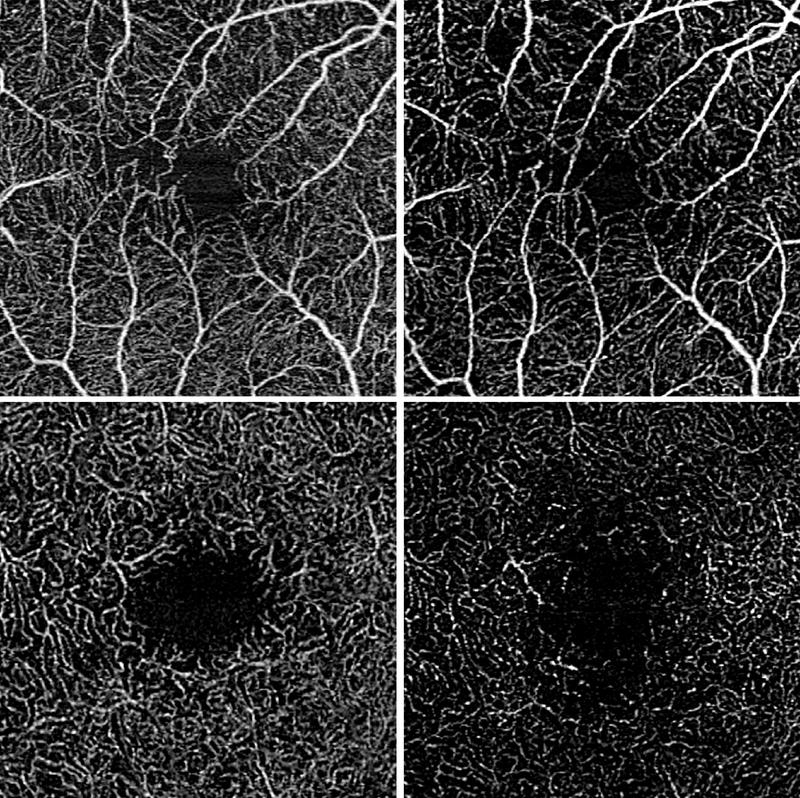

„Mittels der optischen Kohärenztomographie Angiographie ist die berührungslose, nicht-invasive Untersuchung der Netzhaut und der darunterliegenden Aderhaut möglich. Durch unschädliches schwaches Laserlicht wird die Netzhaut sukzessive abgetastet wodurch Schichtbildaufnahmen der einzelnen Netzhautschichten erzeugt werden können.“, erklärt Wintergerst. Durch Vergleich mehrerer kurz hintereinander aufgenommener Bilder kann der Blutfluss erkannt werden, was Rückschlüsse auf die Durchblutung der Netzhautgefäße zulässt. Anschließend haben die Forschenden des UKB und der Universität Bonn die Durchblutungsdichte der zentralen Netzhaut berechnet und analysiert, wie sich diese zwischen Augen mit stabiler Erkrankung, Augen mit Zunahme der Krankheitsaktivität und Augen mit Abnahme der Krankheitsaktivität unterscheidet. Die Forschenden untersuchten insgesamt 52 Studien-Teilnehmende und konnten zeigen, dass die Durchblutungsdichte zwischen den drei untersuchten Gruppen unterschiedlich war. Eine Zunahme der Krankheitsaktivität ging mit einer Abnahme der Durchblutungsdichte einher, während eine Abnahme der Krankheitsaktivität mit einer Zunahme der Durchblutungsdichte einherging.

Zusätzlich untersuchten die Bonner Forschenden in einem statistischen Modell, in das über 300 Augenuntersuchungen eingeflossen sind, die Vorhersagekraft der aktuellen Durchblutungsdichte für den zukünftigen Krankheitsverlauf. Hierbei zeigte sich, dass eine verringerte Durchblutungsdichte signifikant mit einer zukünftigen Verschlechterung der zentralen Sehschärfe assoziiert war. „Die gewonnenen Daten könnten uns in Zukunft ermöglichen Patienten mit einem hohen Risiko für eine Krankheitszunahme frühzeitiger zu identifizieren, um diese beispielsweise besonders engmaschig zu kontrollieren.“, sagt Prof. Dr. Dr. Robert Finger, Co-Autor der Studie und mittlerweile Direktor der Augenklinik an der Universitätsmedizin Mannheim (UMM). “Wir könnten diesen Parameter in zukünftigen klinischen randomisierten Studien als Endpunkt nutzen, um so möglicherweise besser Evidenz für die Behandlung dieser seltenen Erkrankung zu generieren.“